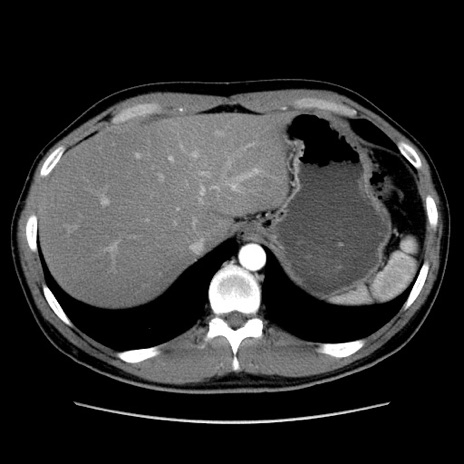

症例36(横断像)

冠状断像

【症例】20歳代 男性

【主訴】心窩部痛

【現病歴】今朝より上腹部痛あり。一旦軽快していたが再度出現したため救急要請。昨日夕に白身の魚を含む刺身を食べた。

【身体所見】BP 136/89mmHg、HR 74/min、BT 37.0℃、腹部:膨満、軟、心窩部に圧痛あり。反跳痛なし、筋性防御なし、腸雑音やや亢進あり。

【データ】WBC 17700、CRP 0.48